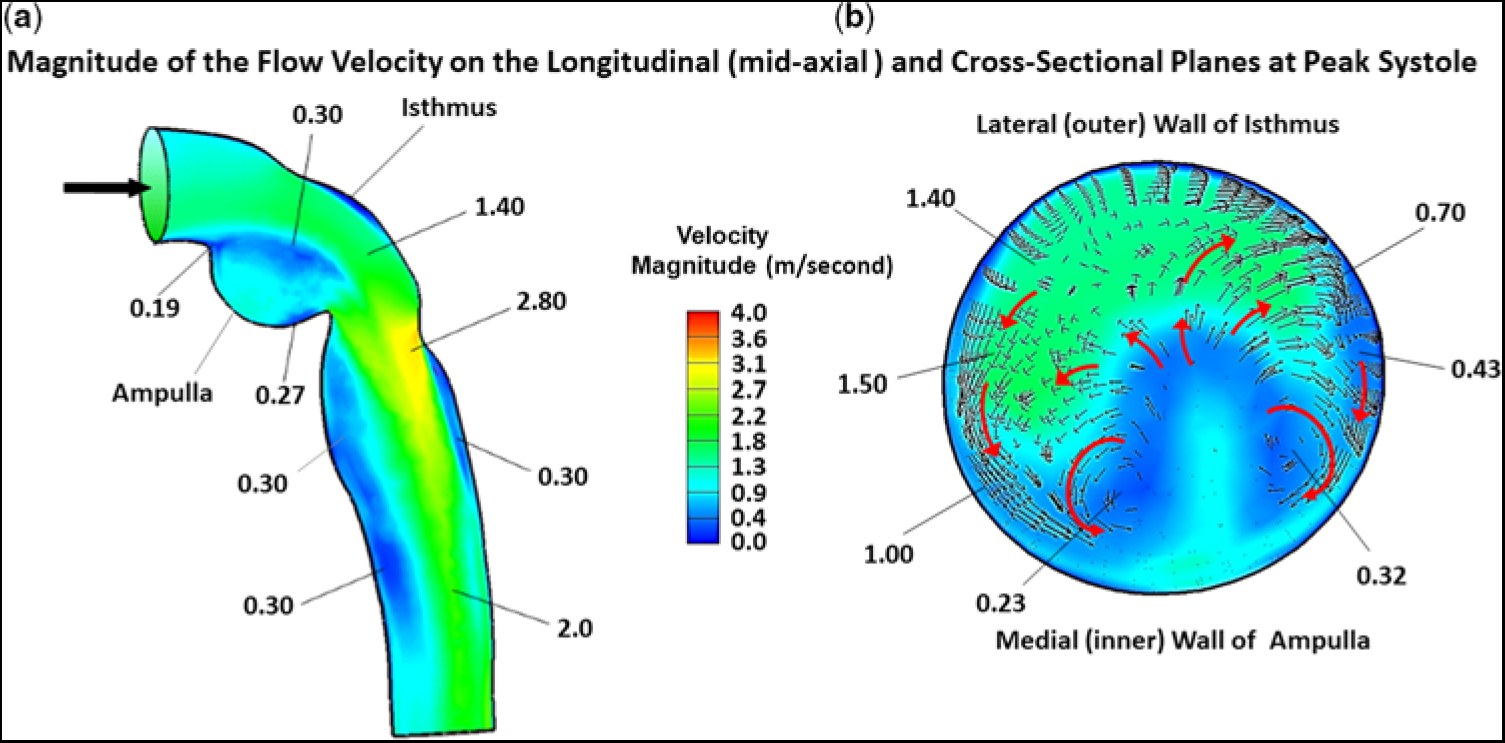

In this study, we focused on flow-velocity distributions and wall shear stresses in the region of re-coarctation, namely the distal transverse aortic arch, aortic isthmus, and thoracic descending aorta. In the ascending aorta and transverse aortic arch, flow was essentially laminar and remained fully attached to the vessel wall, not shown. Flow reversal did not occur, as its inertial force overcame any adverse pressure gradient induced by curvature in the aortic arch. However, the scenario became completely different as flow entered and traversed the ampulla/isthmus, and then the thoracic descending aorta. Figure 3a shows the magnitude of the flow velocity, in metre per second, as distributed over the longitudinal (mid-axial) plane, for the portion of the computational fluid domain of primary interest, at peak systole, and prior to stent implantation. As flow entered the isthmus, it could not abruptly change direction to adhere to the sharply curved wall of the aneurysmal ampulla. Consequently, flow separated from the aortic wall to form a wide, higher-velocity (∼1.4 m/second) stream (green region) that, due to centrifugal effects, travelled along the lateral (outer) wall of the isthmus. This stream gave rise to secondary flow in the ampulla/isthmus that consisted of counter-rotating vortices in the cross-sectional plane. These vortices ultimately led to re-circulating (retrograde) low-velocity (averaging ∼0.25 m/second) flow in the ampulla (prominent blue region) that eventually induced low shear stress on the wall of the ampulla. The vortices are shown in greater detail in Figure 3b.

Figure 3. Magnitude of the flow velocity, in m/second, as distributed over the (a) longitudinal (mid-axial) plane and (b) cross-sectional plane, for the portion of the computational domain of primary interest, at peak systole, and prior to stent implantation. The small black arrows and larger red arrows denote direction (not magnitude) of flow. In this figure, because of space limitation, representative values of flow velocity are shown without the units. The units are (m/second). The low velocity of (0.19 m/second) is near the point of flow separation from the aortic wall.

Figure 3a also displays the magnitude of the flow velocity, in m/second, as distributed over the longitudinal (mid-axial) plane, that is associated with the higher-velocity stream (green region) exiting the isthmus and entering the thoracic descending aorta. At the junction of the isthmus and the descending aorta, at peak systole, flow contracted, but, because of its increased speed, could not abruptly alter direction to follow the remaining bend in the aorta. Thus, flow again detached from the aortic wall, but now emerged as a high-velocity (∼2.8 m/second) eccentric jet that impinged on the lateral wall of the descending aorta (orange/yellow region). Under these circumstances, the maximum flow velocity was no longer at the centre line. A skewed velocity profile developed, where higher velocities occurred near the lateral wall of the descending aorta. As the eccentric high-velocity jet advanced in the descending aorta, it created re-circulating (retrograde) low-velocity (∼0.3 m/second) flow bilaterally in its wake, for a considerable distance along the medial wall (prominent blue region) and, to a lesser extent, the lateral wall (narrow blue region), of the aorta.

Figure 3b shows the magnitude of the flow velocity, in m/second, as distributed over the cross-sectional plane, positioned about midway along the lateral wall of the isthmus, at peak systole, and prior to stent implantation. This figure displays the re-circulating nature of the fluid currents initiated by the counter-rotating vortices. At this position in the isthmus, the vortex flow covered much of the cross section. The small black and larger red arrows signify direction (not magnitude) of the flow. The higher-velocity (∼1.4 m/second) stream (green region) that flowed adjacent to the lateral (outer) wall of the isthmus, shown previously in Figure 3a, and the more slowly moving (0.23–0.32 m/second) flow (blue region) near the centre of the vortices close to the medial (inner) wall of the ampulla are now displayed in the cross section.